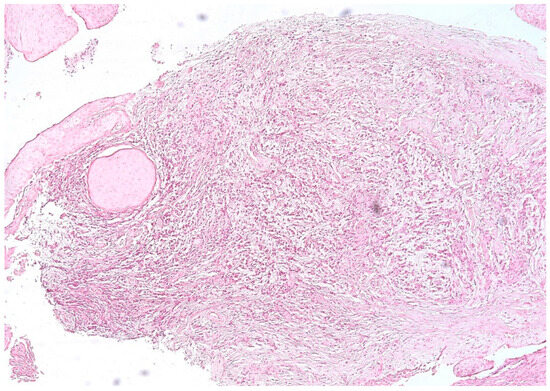

3.1. Morphologic Analysis

3.2. Mast Cells